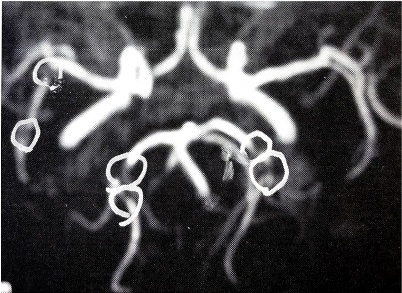

検査はMRIとMRAで行ないます。MRIは脳そのもの状態を、MRAは血管の状態をチェックすることができます。

脳にどんな病気があって、どの部分に損傷があり、どの血管に問題があるのかといったことを読み取ります。

ここでは主にMRAの画像を紹介します。脳血管のどの部分が詰まっているか、どこが狭窄しているか、MRAの画像から読み取り治療による変化の参考にして下さい。

まず、MRAによって脳内動脈がどんなふうに見えるか、P羽に写真で示しました。

正常な人の脳血管

狭窄のある脳血管

白く光っているのが血液が流れている血管です。白い線が写真のようにつながっていれば血管は正常ですが、狭窄を起こしているところは、白だった部分が薄くなったり黒くなったりしています。脳梗塞を起こせば、その先には血流がありませんから、血管は映りません。 こういった脳梗塞の前兆を見逃さず、病気になる前に治療を開始することでリスクを回避することができるのです。治療実例 69歳 男性 Aさん

MRAにて両側の中大脳動脈部に狭窄がみられ、

また後大脳動脈部にも虚血巣がみられた。

そこで、点滴療法を施行した。

10日間の点滴静注により動脈血管の狭窄は著しく改善し、

患者の訴えもほとんどなくなった。